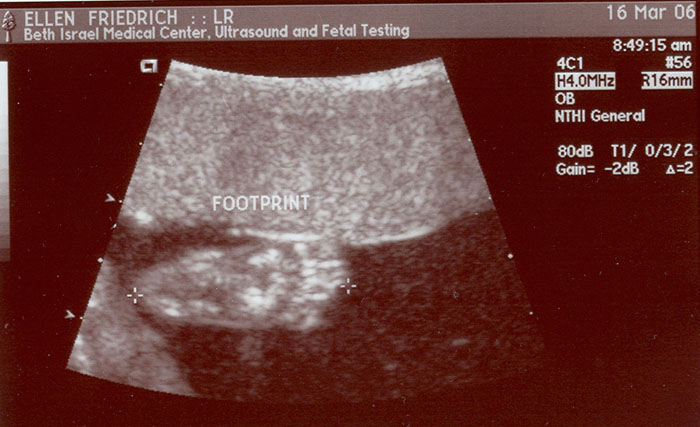

Photo 1 - a Start-  Jan 20 -